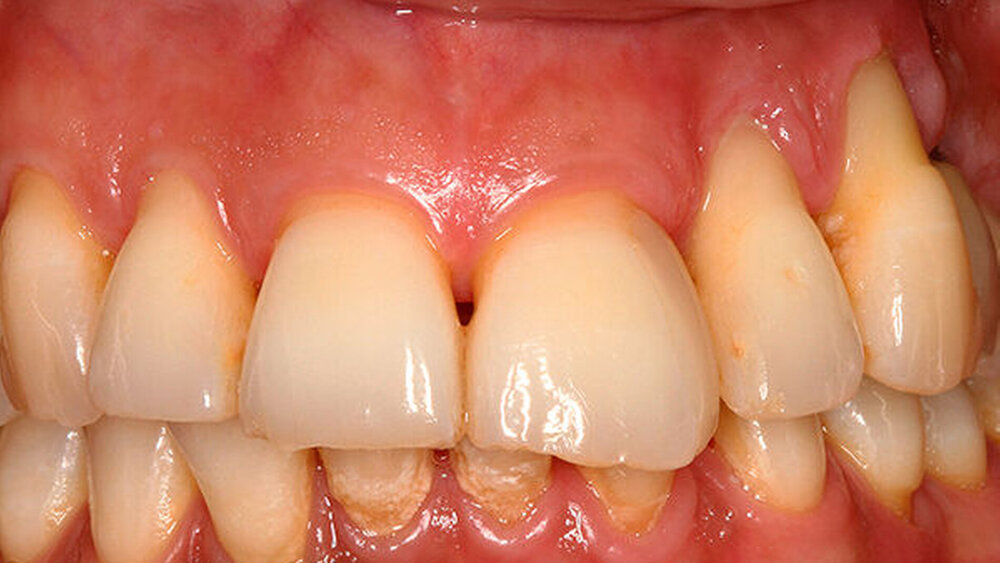

Spätestens mit den neuen, speziell für die Sofortimplantation konzipierten Implantatsystemen wird sich das aber ändern. Allein die hohe Primärstabilität schafft enorme Sicherheit. Ich implantiere seit mehr als 20 Jahren, und ich habe anfangs genau aus den von den Kollegen genannten Gründen einen großen Bogen um die Sofortimplantation gemacht. Von Kollegenansichten und der damaligen Lehrmeinung geprägt, hielt ich die Risiken – vor allem mit Blick auf das ästhetische Outcome – für deutlich zu groß. Wo landen der Knochen und das Weichgewebe tatsächlich? Die Frage hat uns damals abgeschreckt.

Definitiv! Schließlich beschäftigen wir uns seit Jahren intensiv mit dem Thema Knochenerhalt. Ich bin in Sachen Sofortimplantation deutlich mutiger, weil ich aufgrund intensiver Literaturrecherche und der Kenntnis der Indikation und ihrer biologischen Grenzen weiß, welche Vorteile die Sofortimplantation bringt. Dazu beigetragen haben, wie gesagt, die neuen, für Sofortversorgungsprotokolle konzipierten Implantatsysteme wie das BLX …

Eher nicht, man entscheidet sich nicht für die Sofortimplantation, um ein bisschen Zeit zu gewinnen, sondern um das Weichgewebe zu stützen, um die schöne Weichgewebsarchitektur nicht zu verlieren. Sprich: Zur Sofortimplantation gehört auch meist eine Sofortversorgung …

In heiklen Situationen, also im Frontzahnbereich, gingen bestimmt acht Jahre ins Land, bevor ich mich darauf eingelassen habe. Zu dem Zeitpunkt hatte ich sicher mehr als 1000 Implantate gesetzt. Heute bieten wir nach der entsprechenden Fallselektion die Sofortversorgung an.